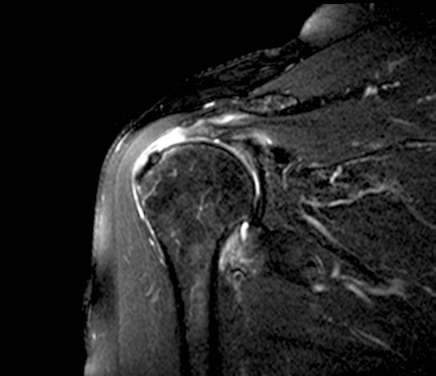

d. Cộng hưởng từ:

Có độ nhạy và độ đặc hiệu lớn hơn 90% đặc biệt khi có tiêm thuốc tương phản từ cho phép chẩn đoán các rách bán phần bề dày mặt hoạt dịch, mặt khớp hay trong gân

Hình 9: MRI khớp vai có bơm thuốc cản từ cho thấy đầu gân rách tụt vào trong, thuốc cản từ màu trắng nằm ở bên ngoài